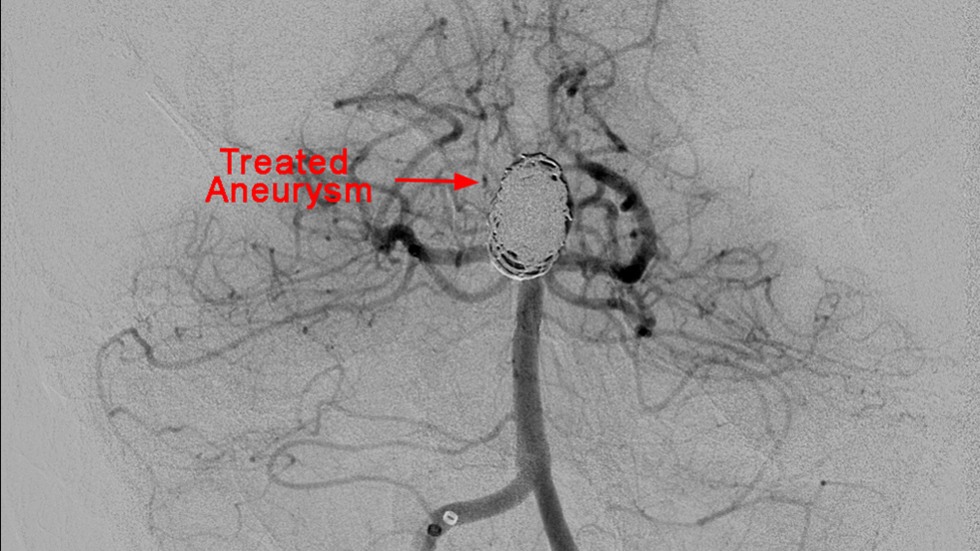

Technique: Treated Aneurysm

3 of 3

Intrasaccular: 1a

Intrasaccular

Intrasaccular: 2a

2 of 6

Intrasaccular: 1b

4 of 6

Intrasaccular: 2b

5 of 6

Intrasaccular: 3b

6 of 6